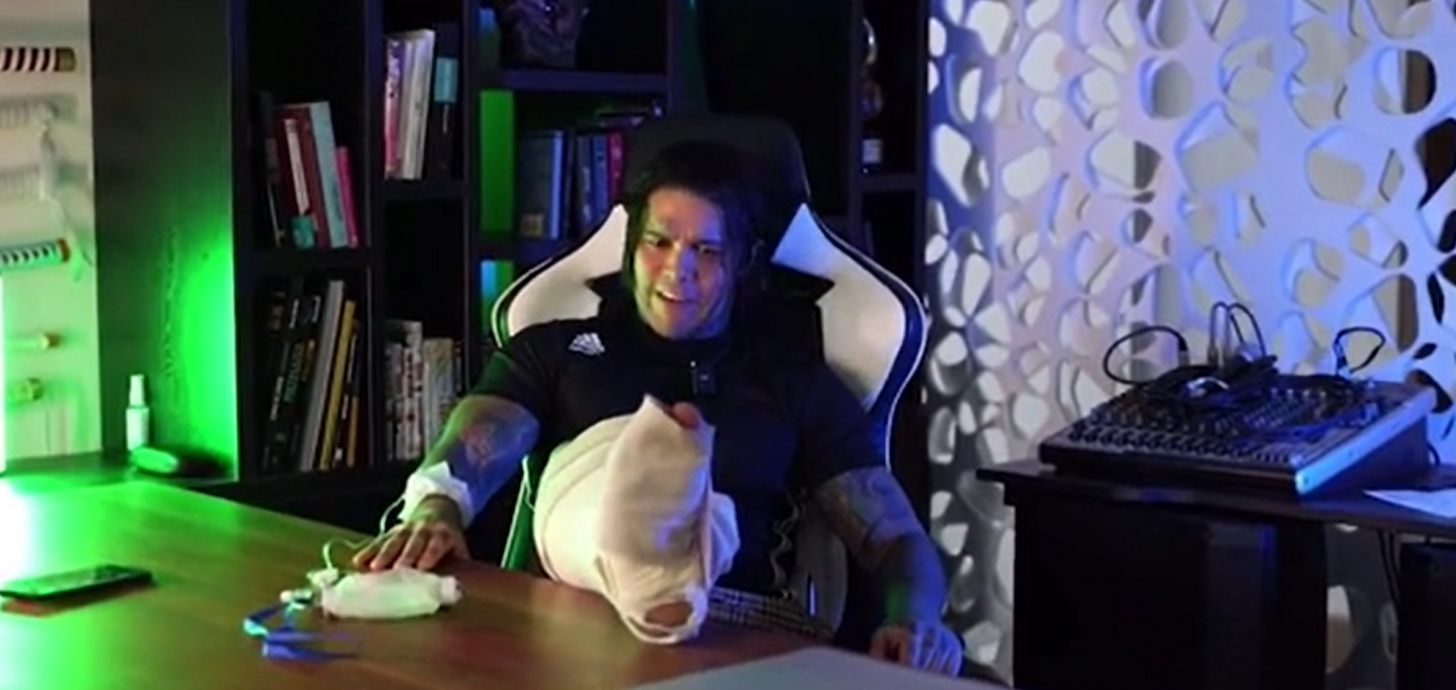

哥倫比亞一名在IG有逾1,100萬名追隨者的男網紅,斥約7億哥倫比亞披索(約130萬港元),接受斷骨增高手術。該手術號稱為「全球最痛手術」,男網紅親身體驗亦證實所言非虛,為了增高4吋而須忍痛4個月,並自爆每晚也會被痛醒,最多只能睡兩小時。

科西奧早前談及感受時直言痛到睡不到覺,「我目前睡不好,正常我每日可睡4至6小時,但過去11至12日,我最多只睡到2小時」,「通常每隔15至20分鐘就會被痛醒,食安眠藥也沒用,不斷痛醒令我崩潰」。他說擔心自己遲早會痛到支持不住,幸好本月25日他便可以拆除支架「甩難」。目前須坐輪椅的他,之後尚須接受復康治療,重新學習行路及跑步。